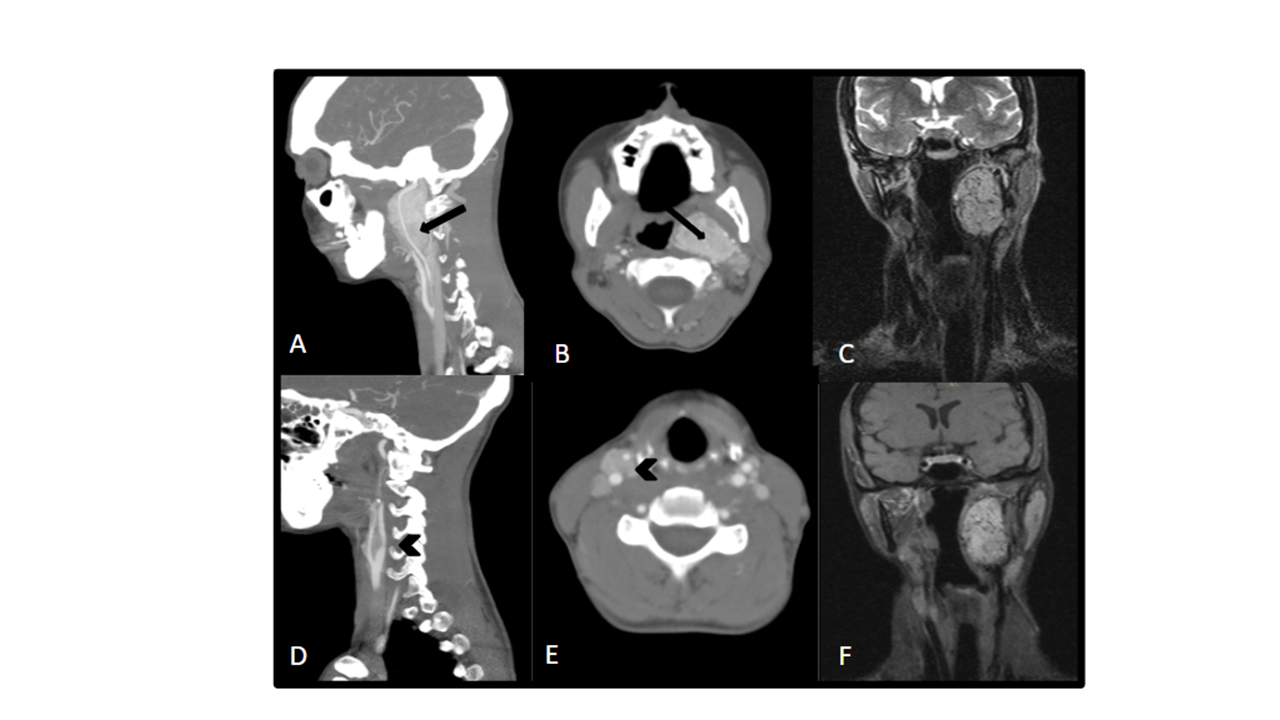

A y B) TC con contraste ev sagital (A) y axial (B): lesión redondeada bien definida con realce arterial situada posteriormente a la bifurcación carotídea (ver flecha), que desplaza tanto la carótida externa como la carótida interna anteriormente, separándolas de la vena yugular y sin ampliar espacio entre ambas, correspondiente a paraganglioma vagal izquierdo. Desplaza la faringe medialmente.

D y E) TC con contraste ev sagital (A) y axial (B): tumoración de partes blandas situada en bifurcación carotídea derecha que provoca apertura de bifurcación carotídea (punta de flecha) compatible con paraganglioma carotídeo derecho.

C) Secuencia coronal T2 con saturación de grasa: Vacío de señal dentro de la tumoración por alta vascularización de la misma

F) Secuencia coronal T1 con saturación grasa + contraste: Tumoración bien definida que presenta realce intenso